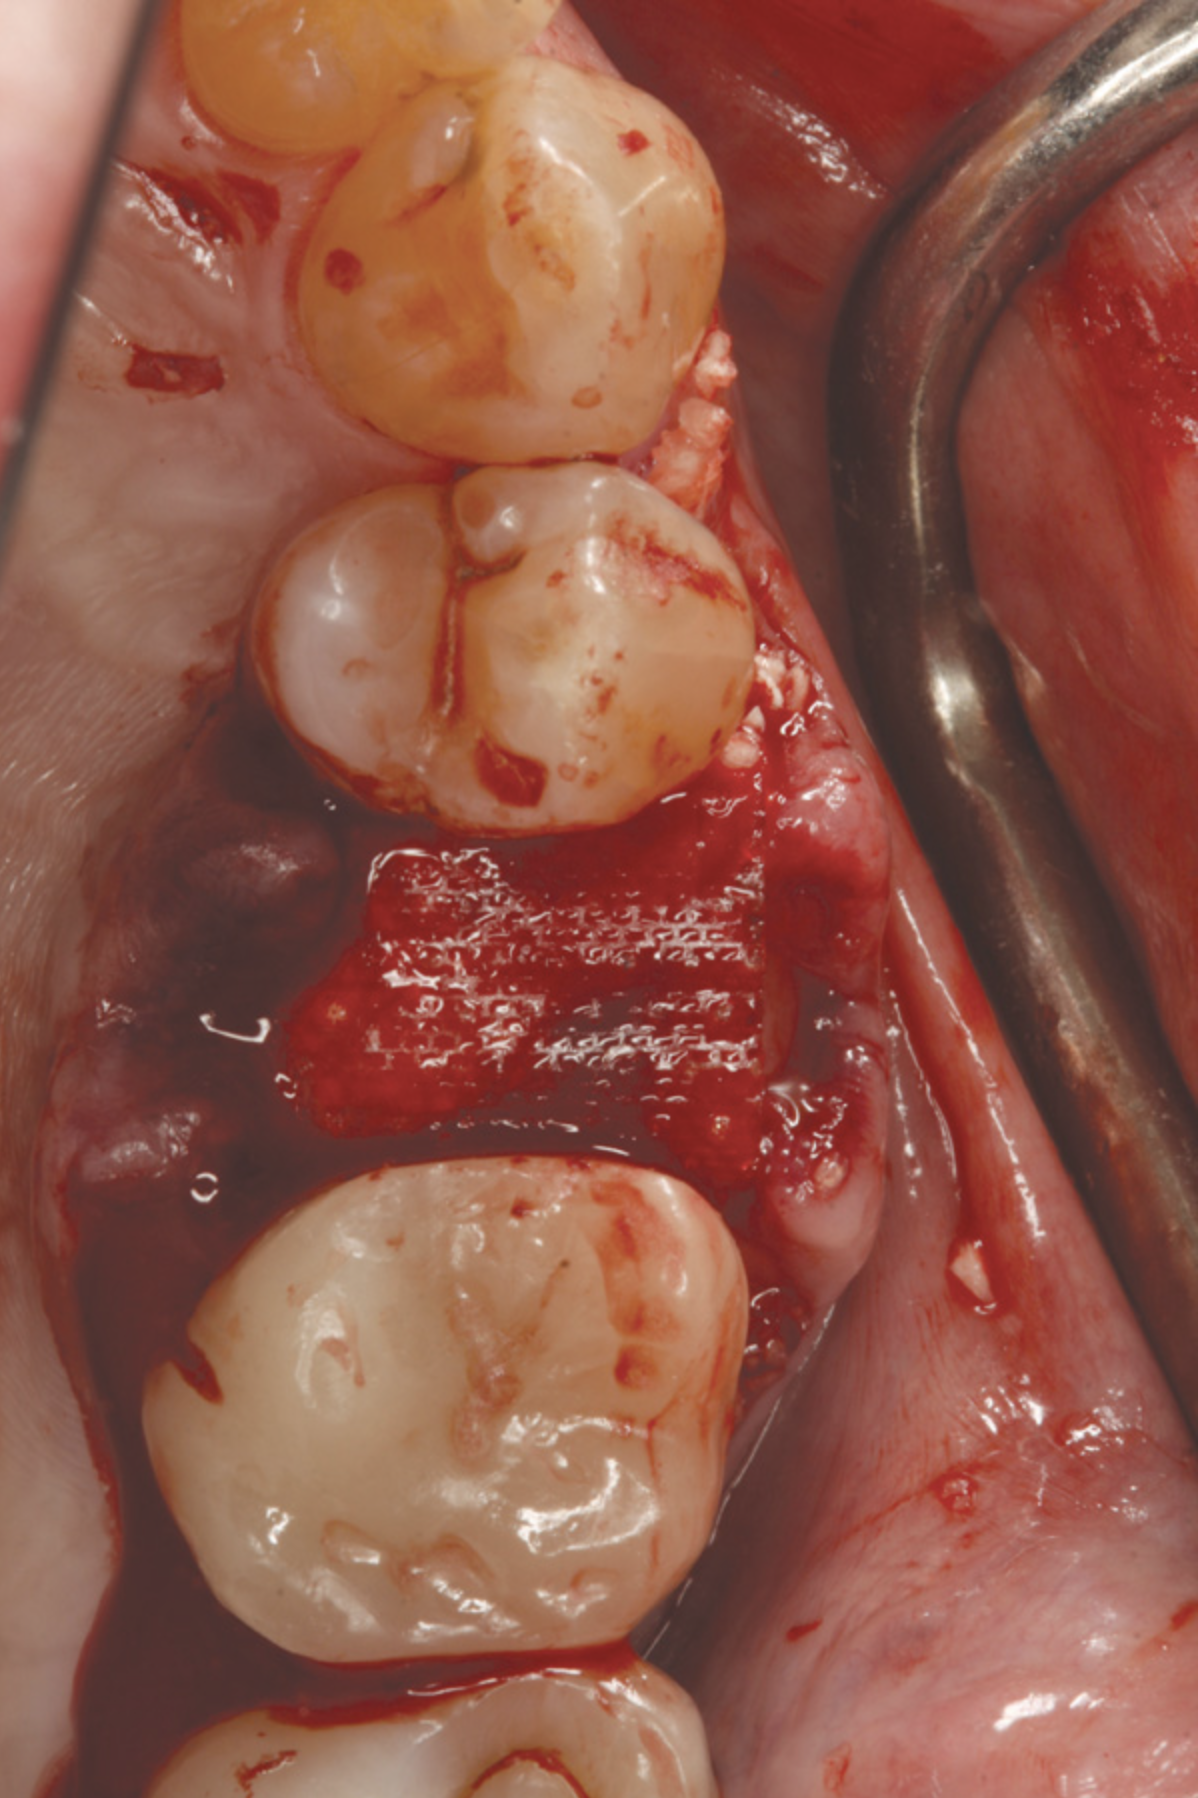

Fig 9. A semi-rigid synthetic barrier was inserted in a subperiosteal manner where a significant loss of palatal bone and thin buccal plate existed.

Figure 9

Fig 10. The deficient socket was grafted and the barrier trimmed and positioned over the bone replacement graft material, enabling ideal formation of the final ridge shape.

Figure 10

In a case presented in Figure 9 through Figure 11, the synthetic barrier was inserted at the time of removal of a tooth with significant bone loss on the palatal aspect (Figure 9). The rigidity of the material not only enabled containment of the bone replacement graft material, but also the initial formation of the site in the desired alveolar ridge shape (Figure 10). Six weeks later, there was no evidence of inflammation and the area was healing quite well (Figure 11). Not only was the alveolar ridge back to its ideal shape at the crest, but there was also a widened zone of keratinized tissue where primary closure was not attempted over the barrier.